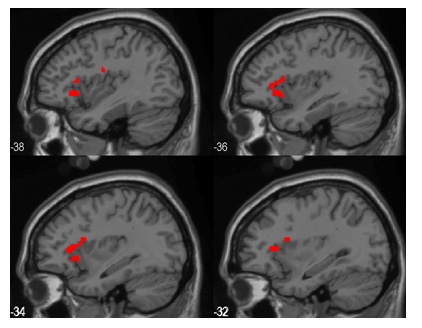

insula anteireure bilaterale